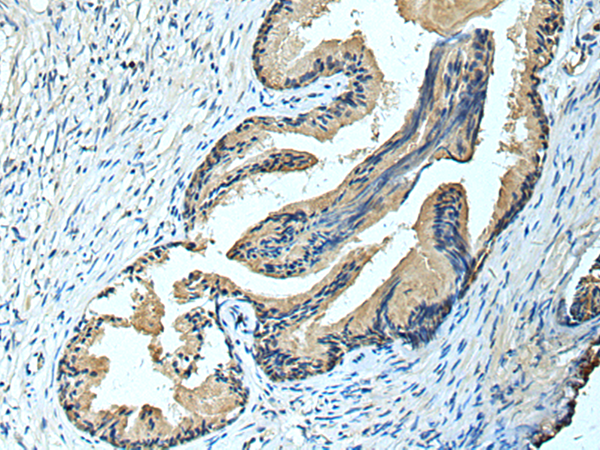

分类: 科研抗体货号: P10405别名: FCRL; FCRX; FREB; FCRL1; FCRLX; FCRLb; FCRLd; FCRLe; FCRLM1; FCRLc1; FCRLc2应用: WB,IHC反应种属: Human